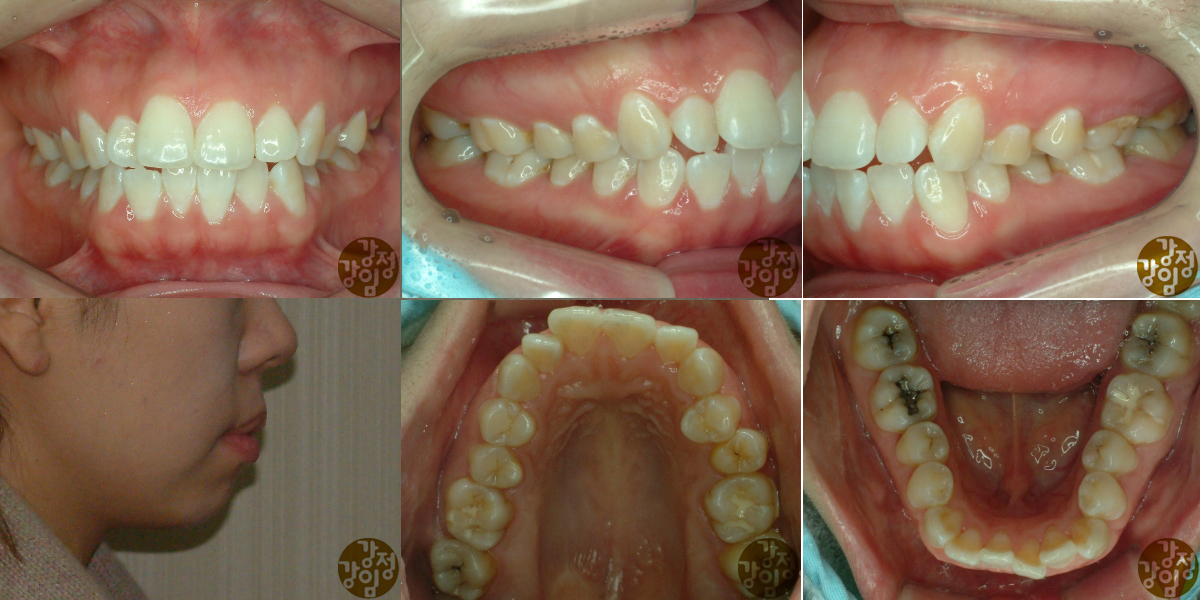

돌출입을 주소로 내원하여 치료한 증례입니다.

안모 변화가 눈에 띄었던 환자라 기억에 남는데,,

교정 장치 제거후 사진이 너무 흐릿하여 홈페이지에 올리기가 좀 그러네요.

아쉬운데로 중간 사진까지라도^^